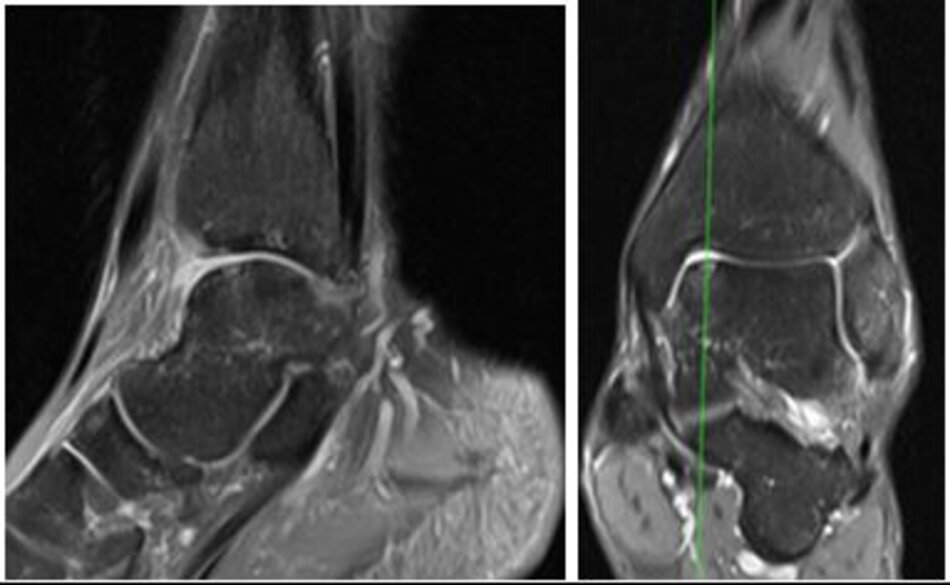

Viêm xương sụn lóc tách

Hình ảnh tổn thương viêm xương sụn lóc tách xương sên trên phim chụp MRI

MRI sau mổ 6 tháng